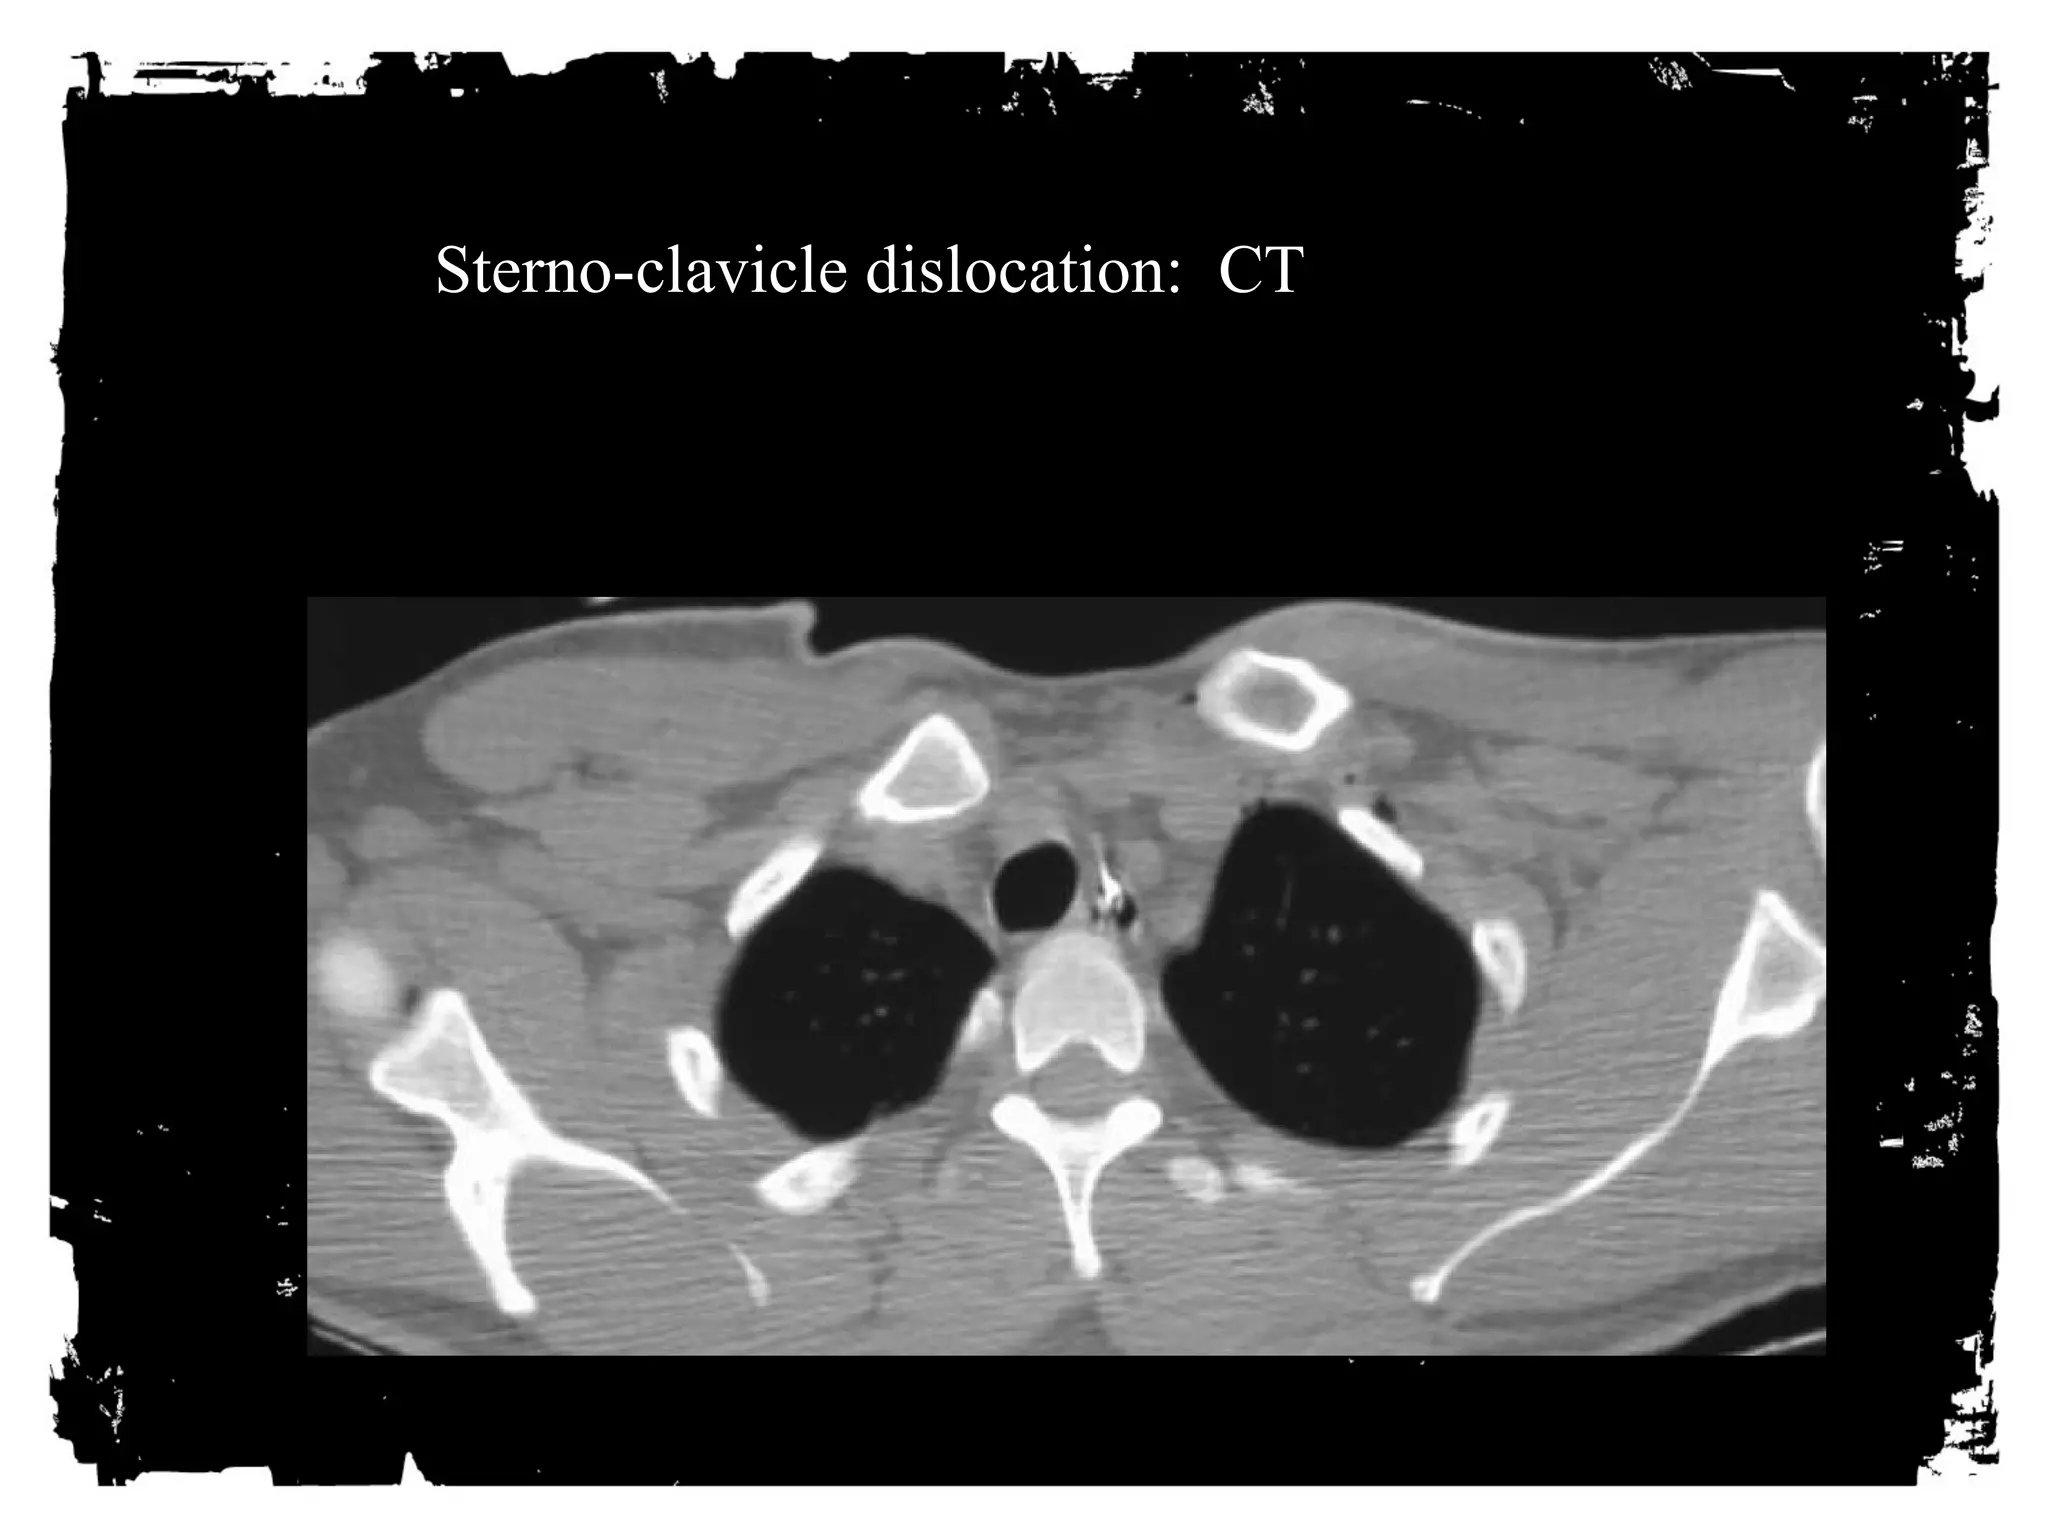

Sterno-Clavicular Dislocations

• Anterior: Not much of a

problem.

• Posterior: Less common; can

injure great vessels or trachea.

Sterno-clavicle dislocation: CT